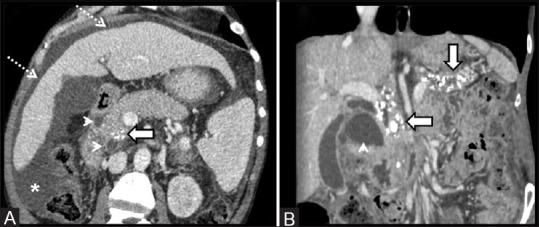

All patients were young to middle-aged men (100%) with history of alcohol abuse (93.9%) and/or smoking (42.4%), who presented either with acute or gradually worsening abdominal pain (90.9%). Pancreatic enzymes and serum tumor markers remained normal or were mildly/transiently elevated. Cystic variant was detected in 57.6% (solid in 42.4%); the disease remained confined to the groove/duodenum (pure form) in 45.4%. Medial duodenal wall thickening with increased enhancement was seen in 87.87 and 81.81%, respectively, and duodenal/paraduodenal cysts were seen in 78.78%. Pancreatic calcifications and biliary stricture were seen 27.3% patients. Peripancreatic arteries were neither infiltrated nor encased.

PP has a discrete predilection for middle-aged men with history of longstanding alcohol abuse and/or smoking. Distinguishing imaging findings include thickening of the pancreatic side of duodenum exhibiting increased enhancement with intramural/paraduodenal cysts. This may be accompanied by plate-like scar tissue in the groove region, which may simulate groove pancreatic carcinoma. However, as opposed to carcinoma, the peripancreatic arteries are neither infiltrated nor encased, rather are medially displaced.

所有患者均为中青年男性(100%),有酗酒史(93.9%)和/或吸烟史(42.4%),表现为急性或逐渐加重的腹痛(90.9%)。胰腺酶和血清肿瘤标志物保持正常或轻度/短暂升高。57.6%检测为囊性变(42.4%为实性);45.4%的疾病局限于沟/十二指肠(纯形式)。分别有87.87%和81.81%的患者出现十二指肠内侧壁增厚且强化增加,78.78%的患者出现十二指肠/十二指肠旁囊肿。27.3%的患者出现胰腺钙化和胆管狭窄。胰周动脉未受侵犯也未被包绕。

PP对有长期酗酒和/或吸烟史的中年男性有明显偏好。具有鉴别意义的影像学表现包括十二指肠胰腺侧增厚,壁内/十二指肠旁囊肿强化增加。这可能伴有沟区的板状瘢痕组织,可能类似沟部胰腺癌。然而,与癌不同的是,胰周动脉未受侵犯也未被包绕,而是向内侧移位。